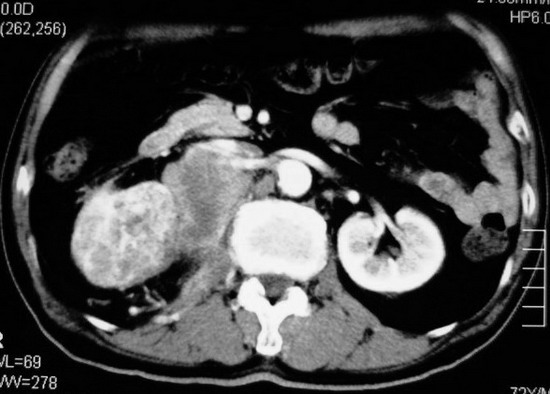

以下是引用杀毒软件在2008-11-17 19:15:00的发言:[br]考虑------右肾癌合并肾静脉---同侧肾上腺受侵可能性大

以下是引用zjzjr在2008-11-17 20:45:00的发言:[br]考虑------右肾癌合并肾静脉---同侧肾上腺受侵可能性大及腹膜后淋巴结转移.